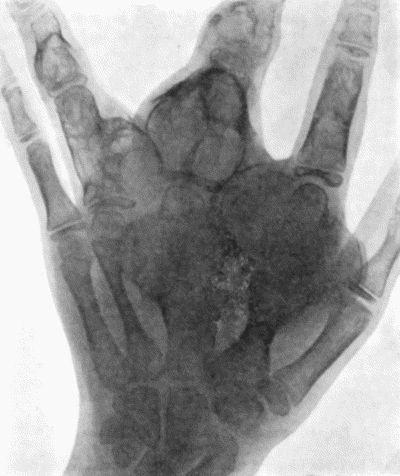

142.Multiple Chondromas of Phalanges and Metacarpals 488

143.Skiagram of Multiple Chondromas 489

144.Multiple Chondromas in Hand 490